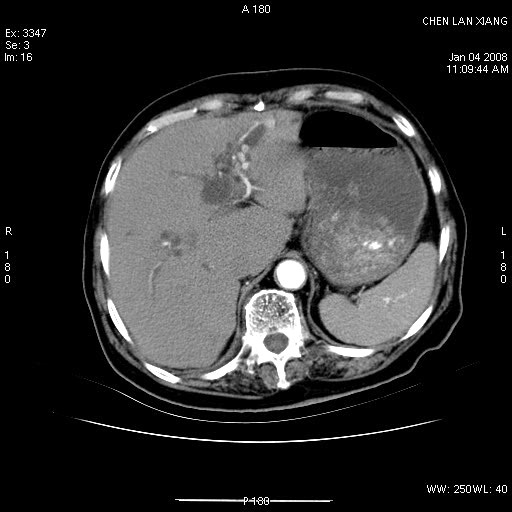

标题: CT11180:女,76岁,腹痛3-4天 [打印本页]

标题: CT11180:女,76岁,腹痛3-4天

女,76岁,腹痛3-4天,b超示:肝内实性肿物,胆囊强回声,胆总管扩张.

1 胆总管末端结石伴肝内胆管结石,肝内外胆管扩张。2 胆囊扩大,胆囊壁不规则增厚,内见软组织密度影。考虑:慢性胆囊炎,不除外胆囊癌!

胆总管末端结石伴肝内胆管结石,肝内外胆管扩张。低位胆道梗阻2 胆囊扩大,胆囊壁不规则增厚,内见软组织密度影。考虑:慢性胆囊炎,不除外胆囊癌!

肝内外胆管多发结石;胆囊癌;

胆囊密度增高,增强后周边肝组织及胆囊窝下部周边软组织延时性不规则强化.然胆囊壁未见明显不规则增厚及肿块.左侧肝内胆管及胆总管下段结石伴胆系扩张.

考虑;胆囊炎(黄色肉芽肿性胆囊炎?),左侧肝内胆管及胆总管下段结石.

1)胆囊癌伴肝脏转移。2)胆总管下端结石、肝内胆管结石伴肝内外胆管扩张。